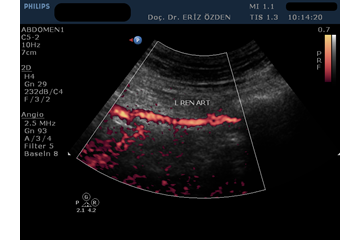

Böbreğe giden atardamarlarda darlık olması durumunda, tansiyon yüksekliği (hipertansiyon) ortaya çıkabilir. Böbrek damarlarının ayrıntılı incelenmesi, darlıkların, tıkanıkların saptanması, böbrek kanlanması hakkında bilgi edinilmesi için Renkli Doppler Ultrason kullanılır. İnceleme sırasında bağırsak gazları görüntüyü bozabileceğinden, hastanın aç olarak gelmesi gereklidir.